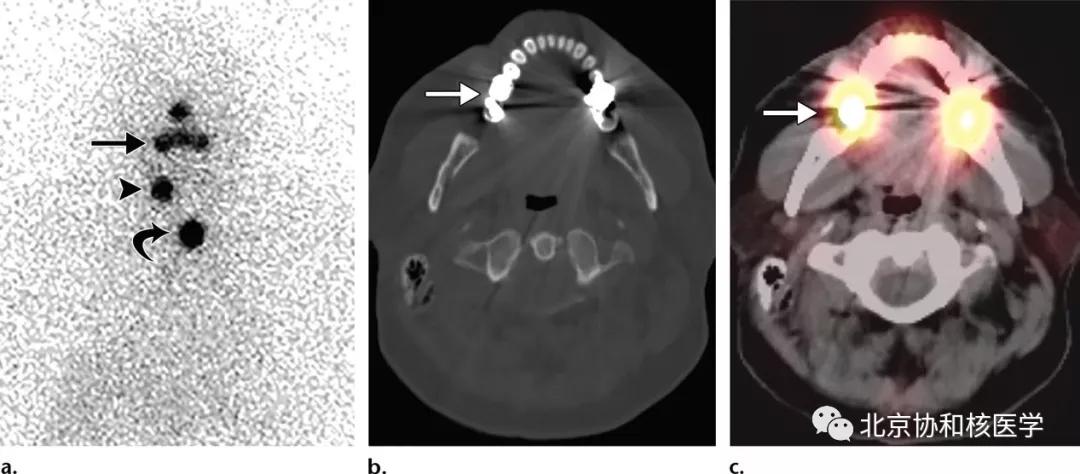

63岁女性,甲状腺乳头状癌甲状腺全切除术后,碘131治疗后,除颈部残余甲状腺外,碘扫见右侧腮腺软组织密度结节,摄取明显增高,穿刺活检提示腮腺良性肿瘤[2]: